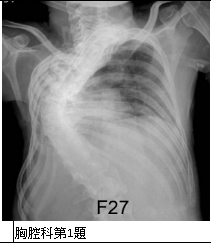

8. 病人是28歲家庭主婦,曾有孕期高血壓及流產兩次。住院前有一個多月開始呼吸困難,其後逐漸加重且伴有食慾不振,偶有端立性呼吸困難,咳嗽,終至雙腳水腫及減少尿量。理學檢查:血壓,98/54 mmHg;心跳,131/min;體溫,37.3度;呼吸36/min;急病狀,貧血眼瞼;雙側肺部有濕囉聲;心臟擴大,有Gr.III/VI pansystolic murmur在apex及Gr.II/IV early diastolic murmur over right upper sternal border,有S3可聞;腹部未有肝脾腫大;雙腳水腫,皮膚冷汗,有紫斑及出血痕斑,如圖8-1及圖8-2所示。在急性心內膜炎(IE)之臆診下,乃在三小時內分別在左右手探血細菌培養都呈現:viridans streptococci。請問本病人依據Duke Criteria診斷IE的根據是: (A) 2 major criteria (B) 1 major criterion & 3 minor criteria (C) 1 major criterion & 2 minor criteria (D) 1 major criterion & 1 minor criterion (E) 2 major criteria & 2 minor criteria